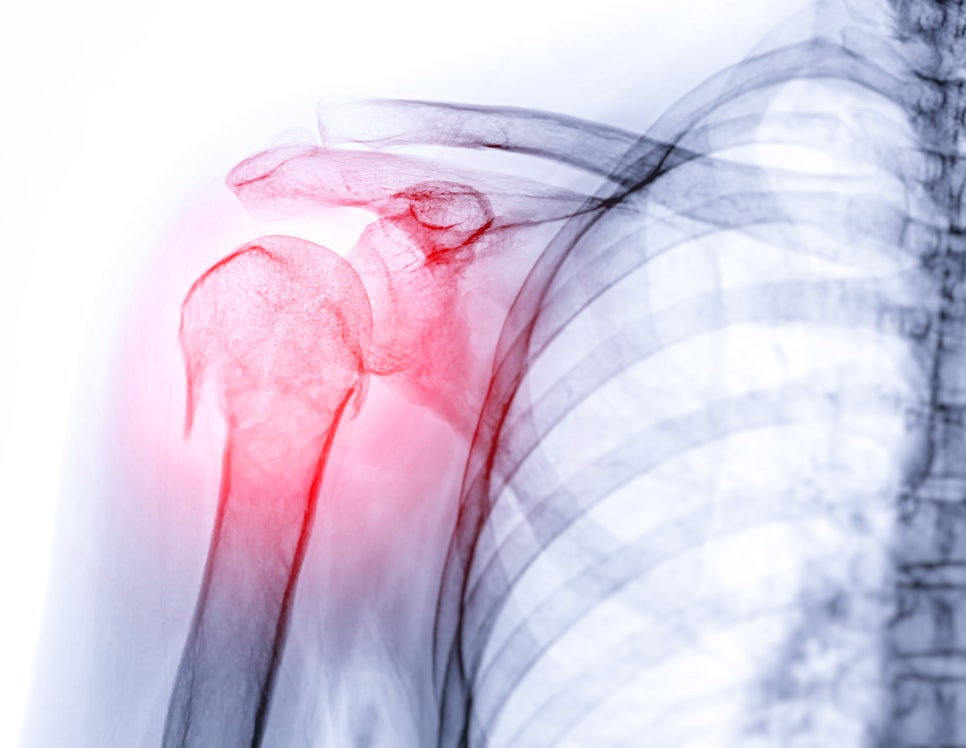

광명21세기병원에서는 환자가 어깨 통증으로 내원하면, 먼저 자세한 문진과 이학적 검사를 통해 증상을 확인하고 있습니다. 이후 필요에 따라 추가적인 검진을 진행할 수 있어요. 이 과정을 통해 단순 근육통인지, 오십견인지, 아니면 회전근개 파열과 같은 다른 질환인지 감별할 수 있는 것이죠.

🟣 X-ray 촬영: 뼈 구조 이상이나 관절 간격 확인

🟣 초음파 검사: 회전근개 힘줄이나 주변 연부조직 손상 여부 확인

🟣 체형·움직임 분석: 어깨 가동 범위 제한 정도, 통증 부위 확인